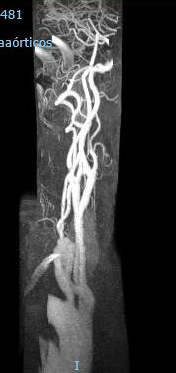

Ecografía Doppler de Troncos Supraórticos

Eje derecho: Velocidad sistólica (cm/s) Carótida Interna (CI) 300; Carótida Común (CC) 64. Relación CI/CC 4,7. Velocidad Diastólica Final (VDF) en la CI 79. Estenosis superior al 70%. Placa heterogénea, irregular, hiperecoica y calcificada. Subclavia normal. Distancia bifurcación normal. Se visualiza CI distal sin alteraciones.

Eje izquierdo: Velocidad sistólica (cm/s) CI 120; CC 92. Relación CI/CC 1,3. VDF CI 30. Estenosis inferior al 50%.

Conclusiones: Eje derecho con abundante ateromatosis de contenido mixto en carótida común y bulbo carotídeo. Estenosis de carótida derecha superior al 70% y estenosis de carótida izquierda inferior al 50%.